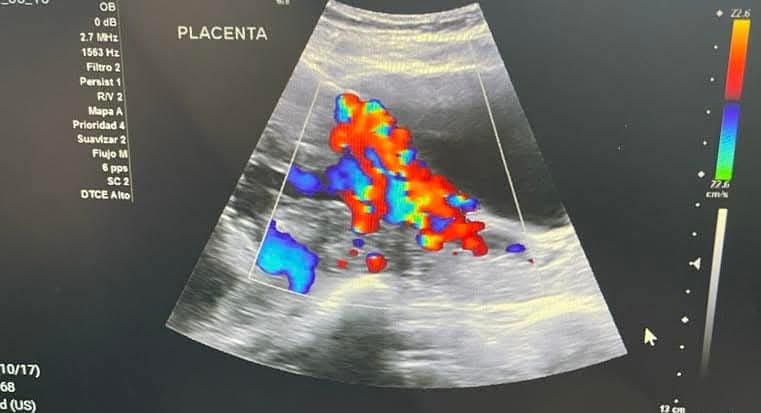

Chacón Lechuga indicó que la mayoría de los casos atendidos son por acretismos placentarios en sus tres niveles: acreta, percreta e increta, es decir, que la placenta está adherida de una manera anormal a la matriz, a otros órganos y a los vasos sanguíneos, lo que puede provocar una hemorragia severa.